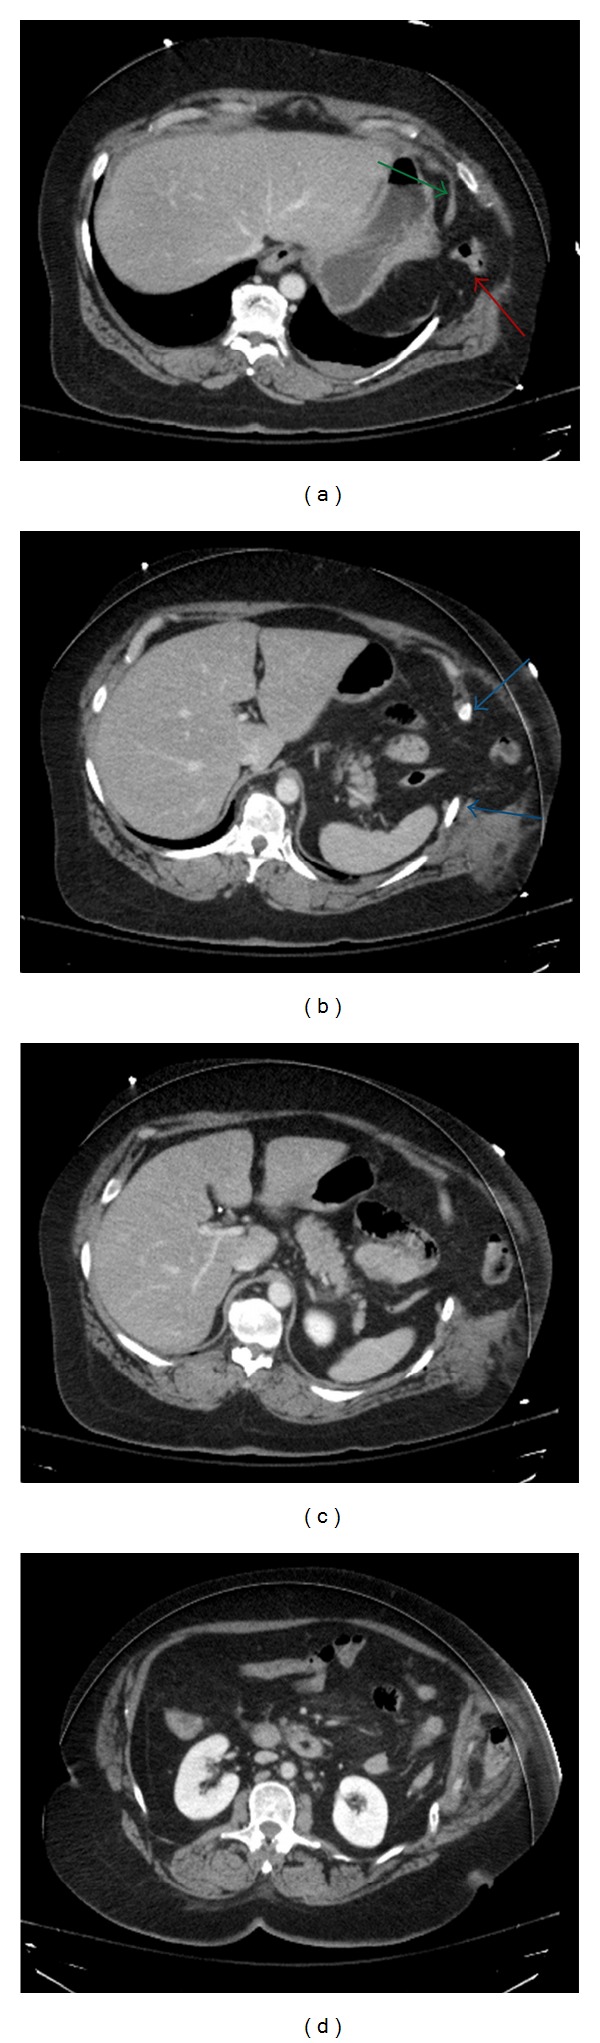

Figure 1.

Axial CT images of the chest demonstrate herniation of lung beyond the thoracic cavity (red arrow) (a). There is discontinuity of the diaphragm (blue arrows) and widened intercostal space (green arrows). Herniation of abdominal contents is present including omentum and transverse colon into the chest and through the intercostal defect (b).